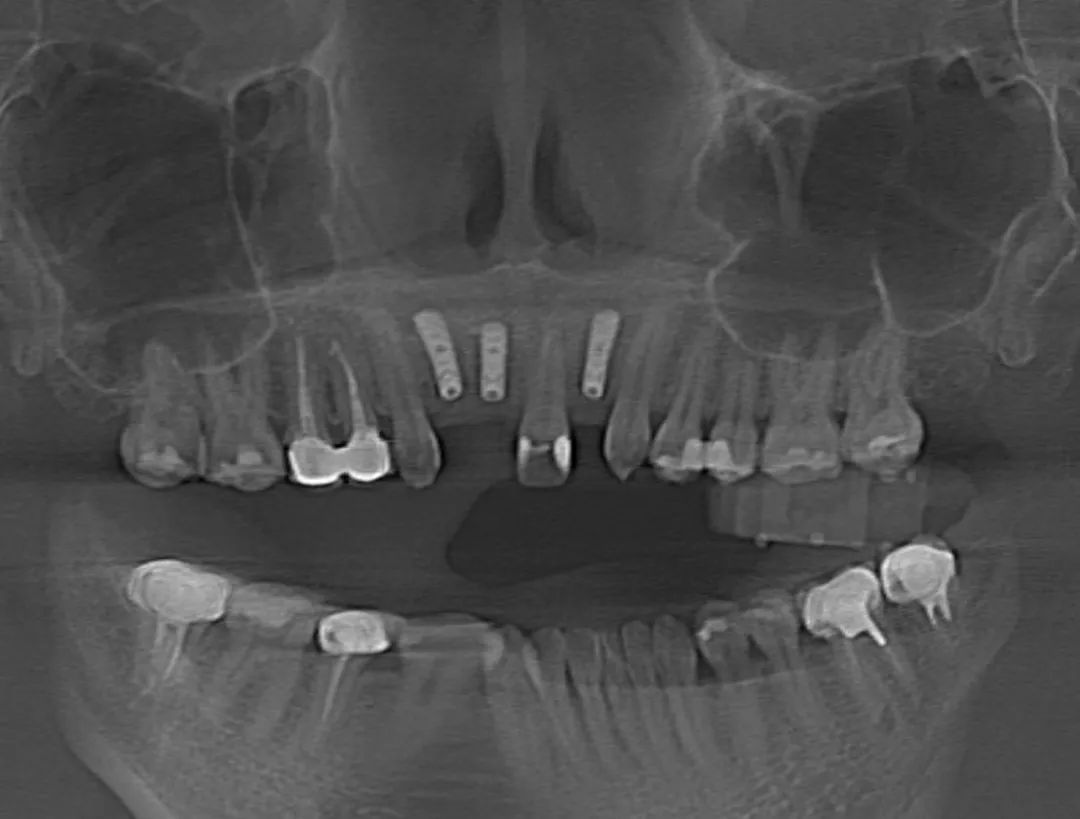

患者术后影像图

术中,高益鸣主任、李小曼医生共同按既定方案,在机器人全自动模式下,精准标定种植位点并逐级扩孔备洞。而且,机械臂的减速区设定,让机器人在入口时动作不会过快,“温柔”且“迅速”地有序按照指令进行手术。手术过程相比传统方式来说缩短了近一半。如今,这位女士恢复良好。